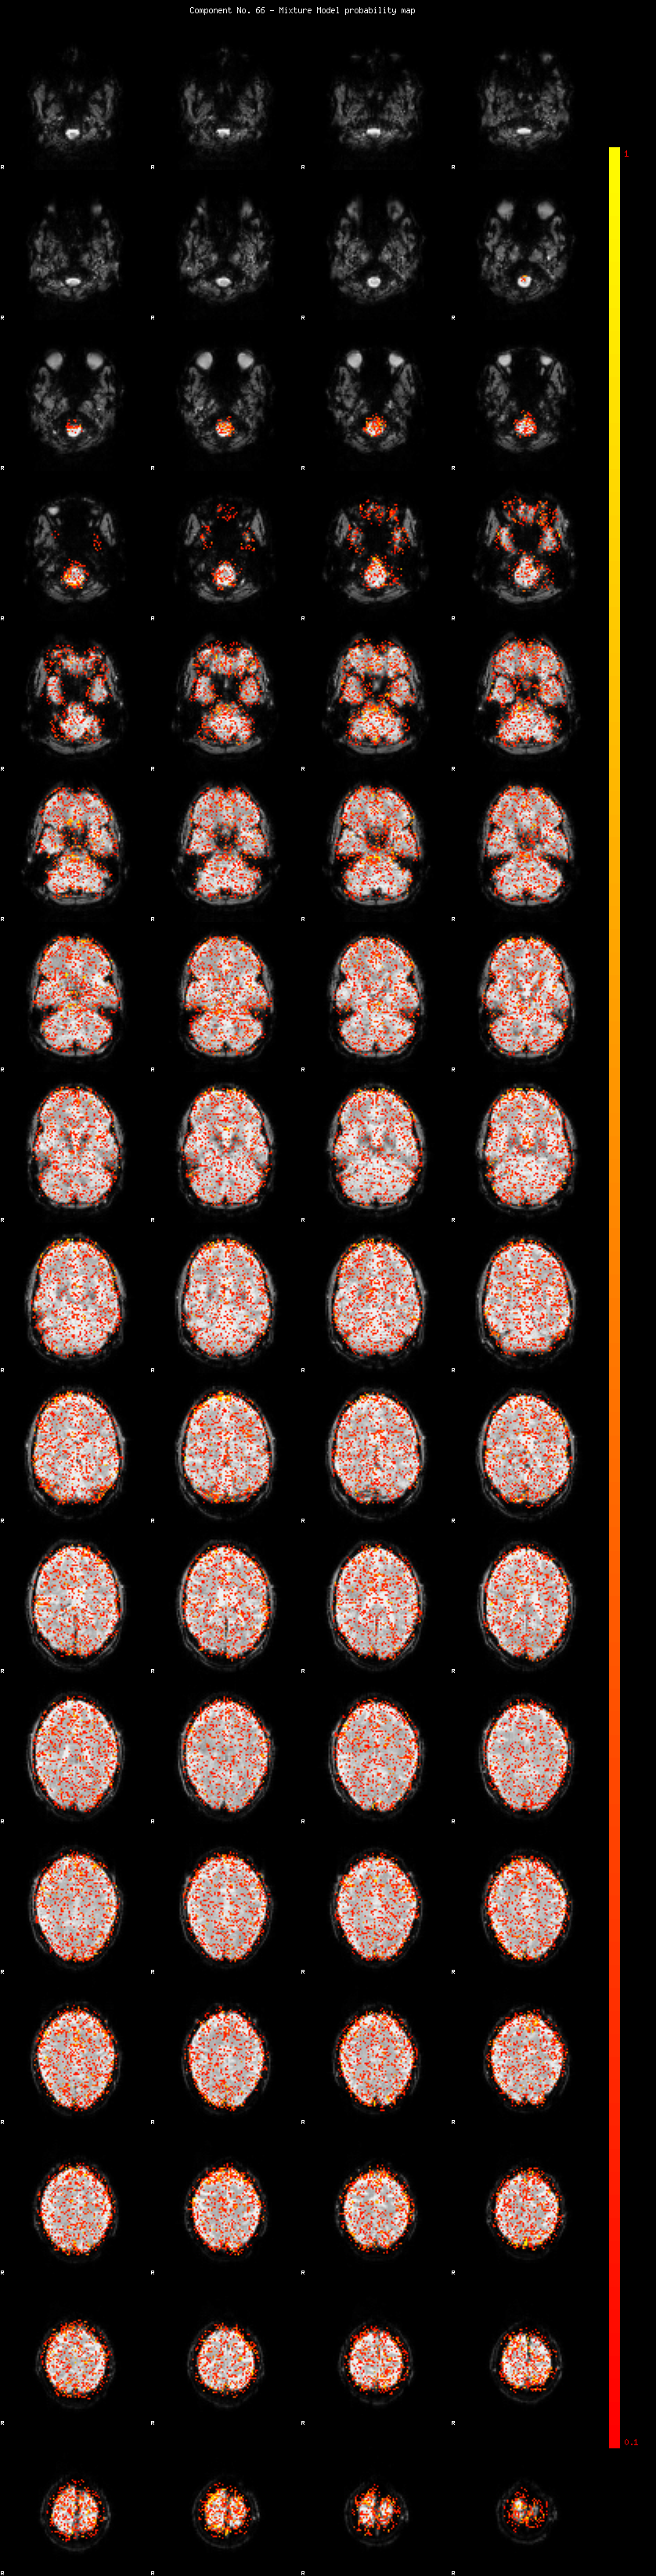

IC_66 Mixture Model fit

Means : 0.000000 2.044433 -2.006305

Vars : 1.000000 0.737991 0.659879

Prop. : 0.919838 0.043988 0.036174

This page produced automatically by MELODIC Version 3.14 - a part of FSL - FMRIB Software Library.